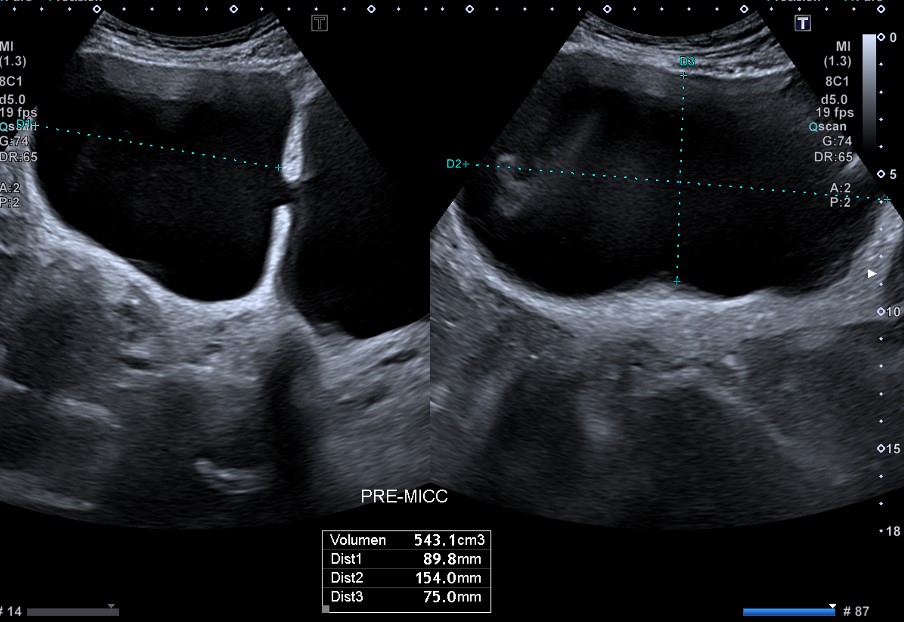

Riñones de tamaño y morfología normales. No observamos litiasis ni dilatación de la vía urinaria. A nivel de la vejiga presenta un tabique con comunicación a una gran cavidad en la pared lateral derecha que da la impresión de que existen dos vejigas urinarias. No hay lesiones parietales. Próstata 32 cc. Volumen premiccional de la cavidad mayor 350 cc y posmiccional 210 cc.

Vejiga urinaria con presencia de jets ureterales, de paredes lisas con un gran divertículo en la pared lateral derecha de 543 cc premiccional que vacía a la mitad en posmiccional 310cc (57%).Volumen vesical premiccional 620cc y posmiccional 179 cc (28%).